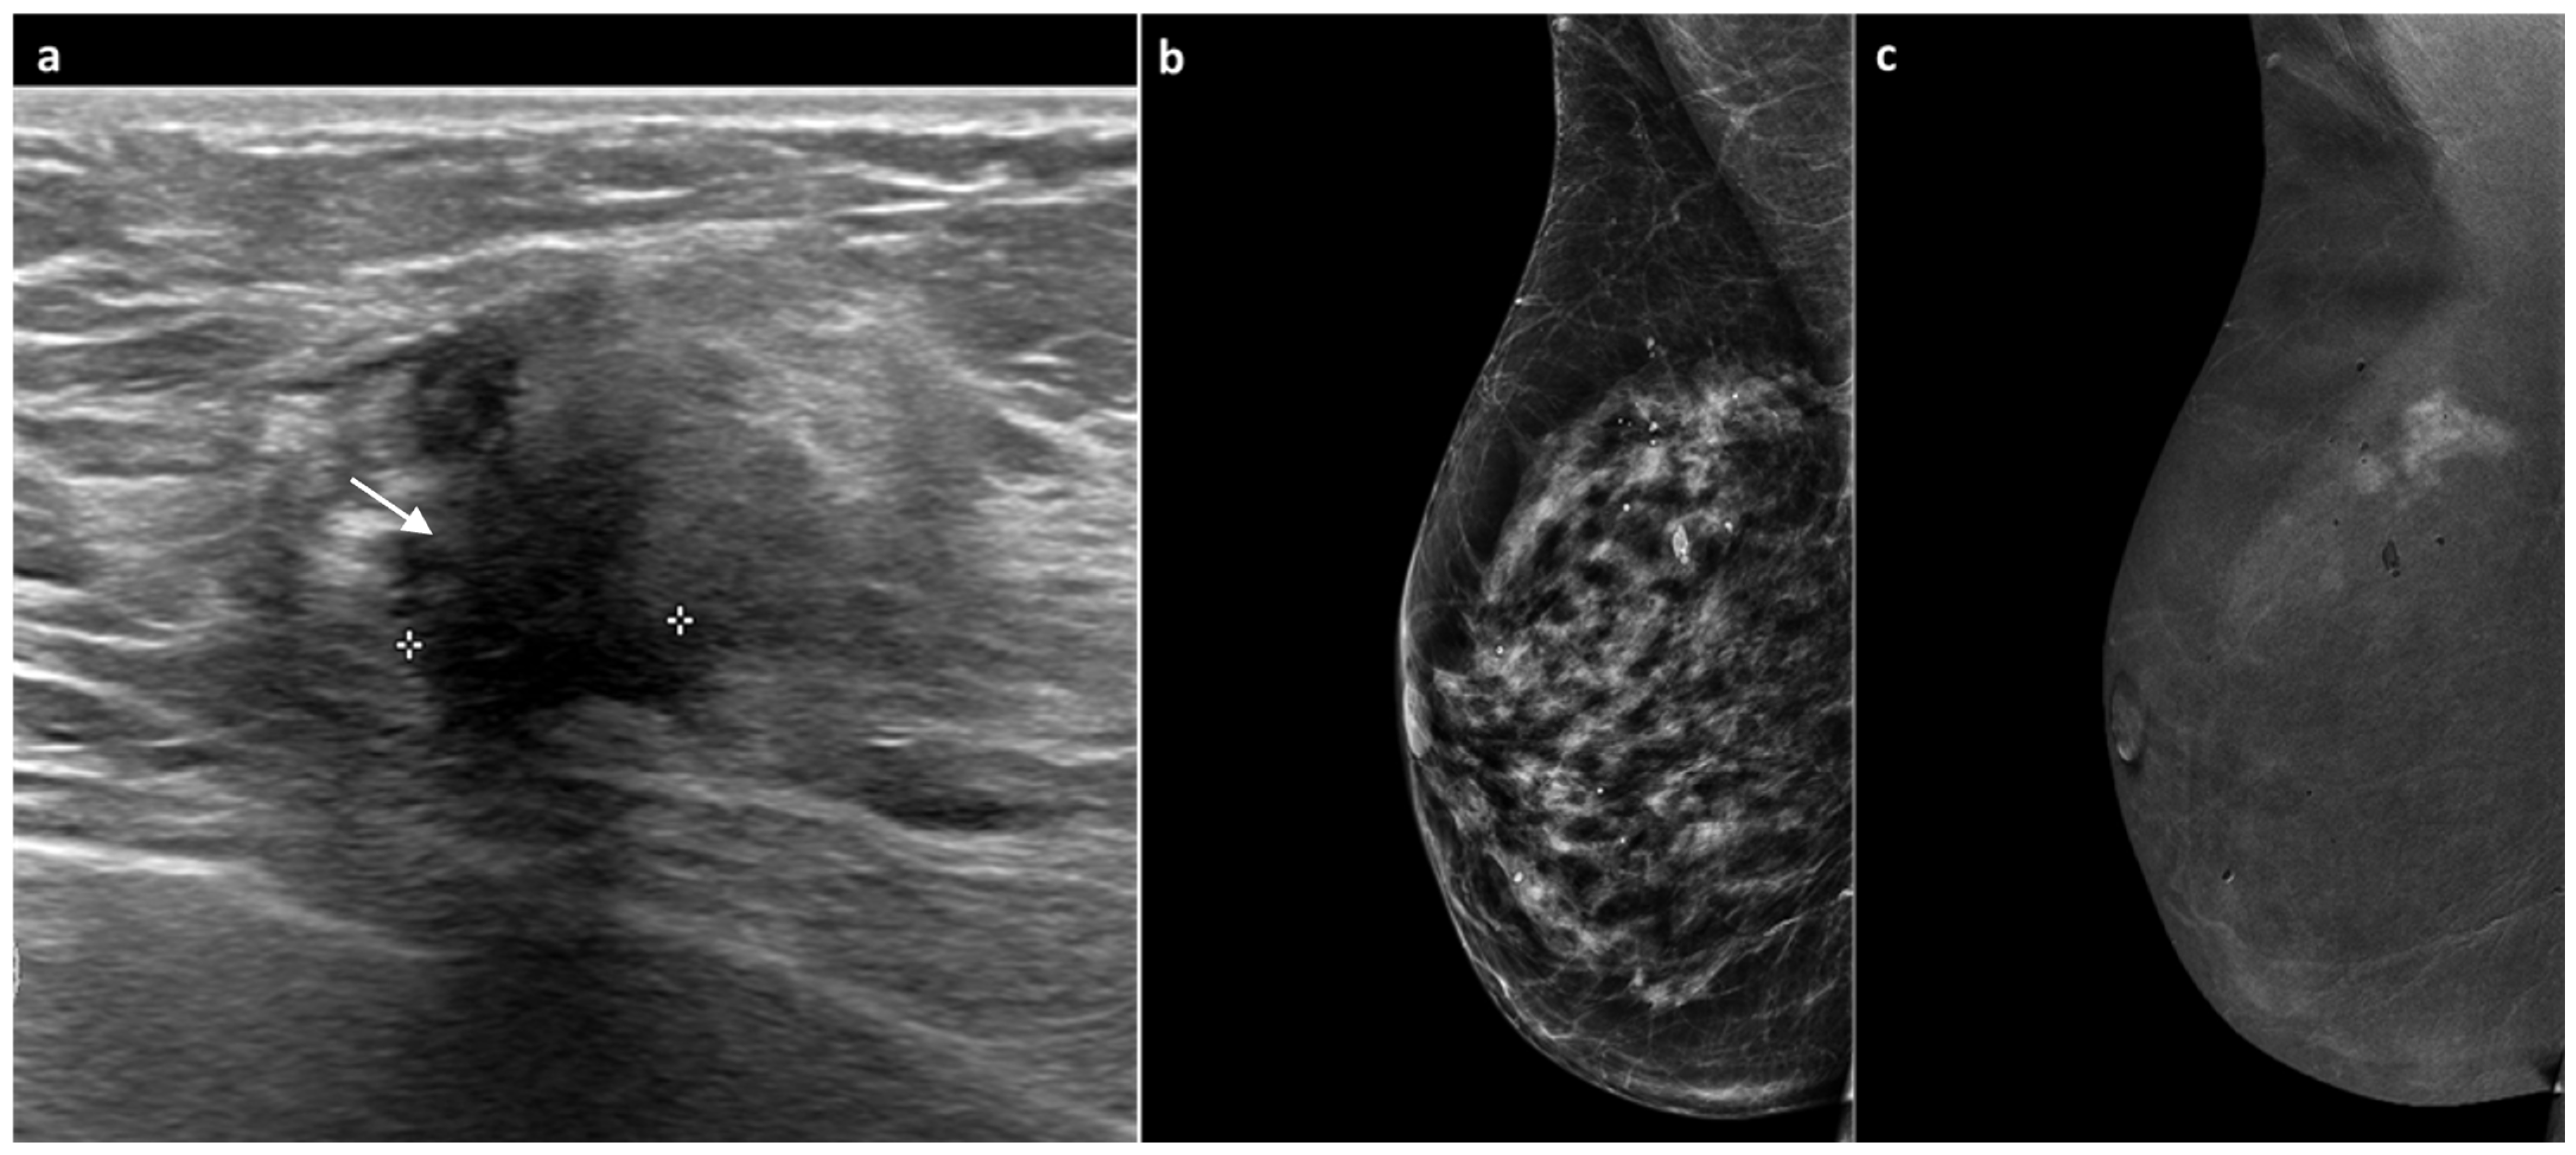

3.2. CEM Examination and Analysis